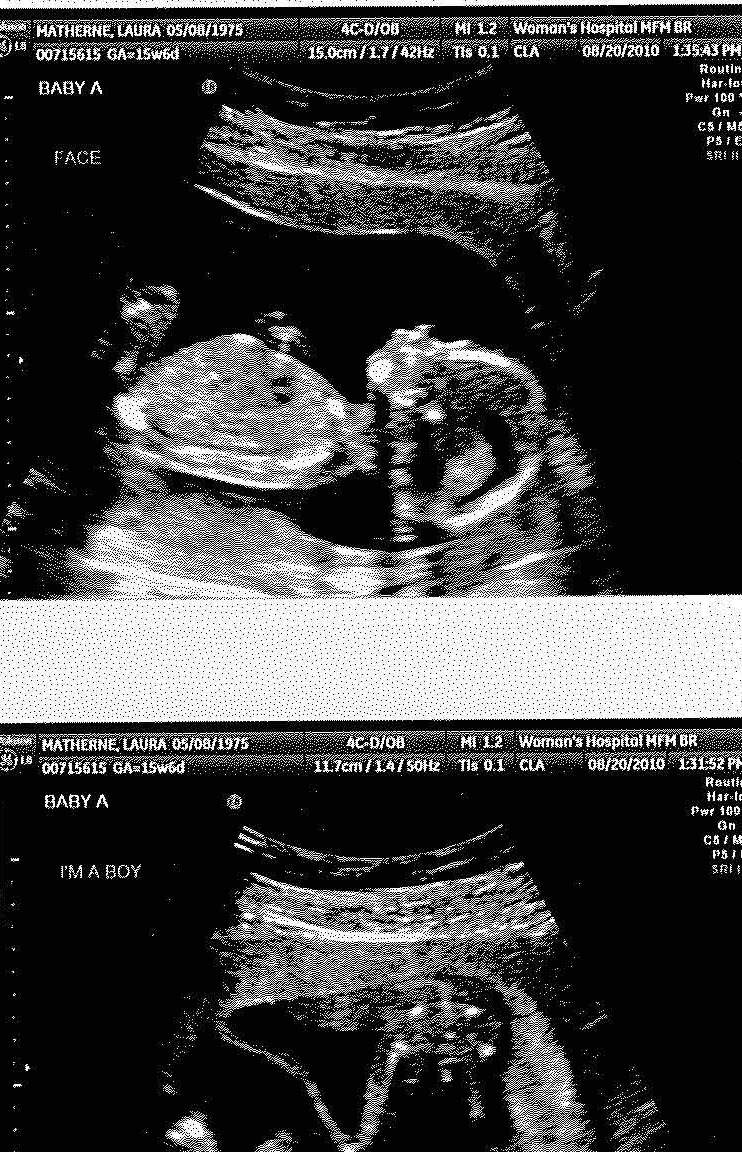

From mathernequads.blogspot.com

The Matherne Quads! 16 week ultrasound Baby A Its a Boy! Baby Boy Ultrasound At 16 Weeks discover what your baby boy's ultrasound will look like at different stages of pregnancy and learn some interesting facts about the making of a boy. There is not a scan at 16 weeks pregnant, but there should, however, be an antenatal appointment. when you are 16 weeks into your prenatal journey, it’s time for an important milestone: . Baby Boy Ultrasound At 16 Weeks.